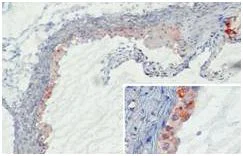

Immunohistochemistry (Frozen sections) - Anti-Mannan Binding Lectin/MBL antibody [14D12] (AB106046)

ab106046 detecting Mannan Binding Lectin/MBL deposition in developing murine atherosclerotic lesions following 10 weeks of high fat feeding. Mannan Binding Lectin/MBL was detected in and around invading macrophages invading the intima (insert). Mannan Binding Lectin/MBL bound at sites of necrosis (upper right corner). No Mannan Binding Lectin/MBL binding was shown in the media or on fibrous caps covering the thickened intima.